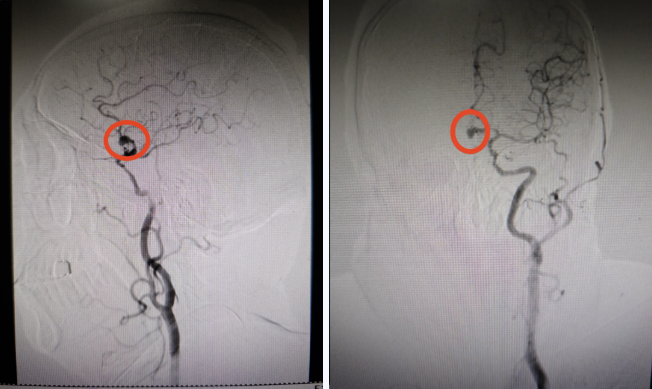

动脉瘤栓塞术前影像

“脑动脉瘤就像脑血管壁上吹起的一个‘小气泡’,壁很薄,一旦破裂出血,致死、致残率极高。”神经内一科周福高主任介绍,“这位患者的情况尤为特殊,多个重要血管同时存在问题,加上他有多年的高血压和糖尿病史,使得这个动脉瘤如同一个‘不定时炸弹’,风险非常大。”